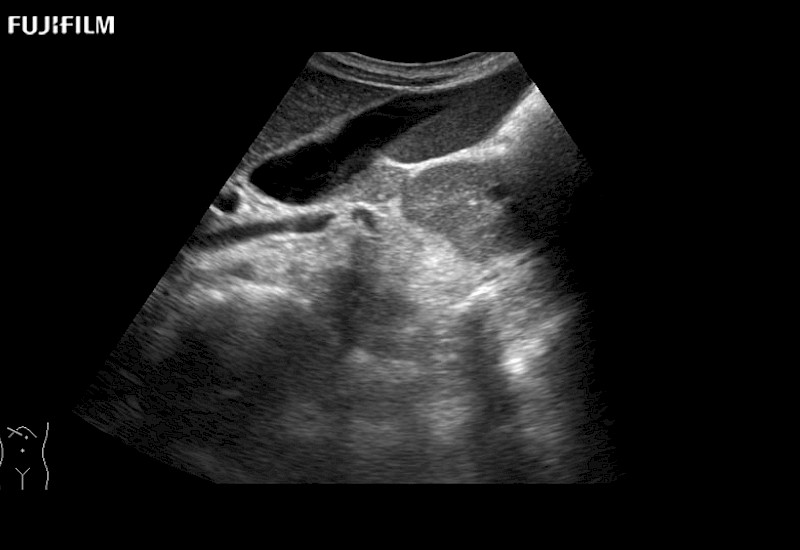

Our dedication to Laparoscopic Surgery allows us to offer superior image quality, outstanding system reliability and intuitive use of cutting edge technology.